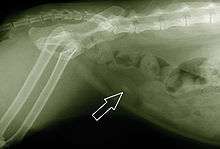

Diagnosis

When symptoms indicate bladder stones, the first step is usually to take an x-ray. Most types of stones will appear readily in an x-ray, urate and occasionally cystine stones being the most common exceptions. Stones smaller than three millimeters may not be visible.[3] Ultrasonography is also useful for identifying bladder stones. Crystals identified in a urinalysis may help identify the stones, but analysis of the stones is necessary for identification of the complete chemical composition.